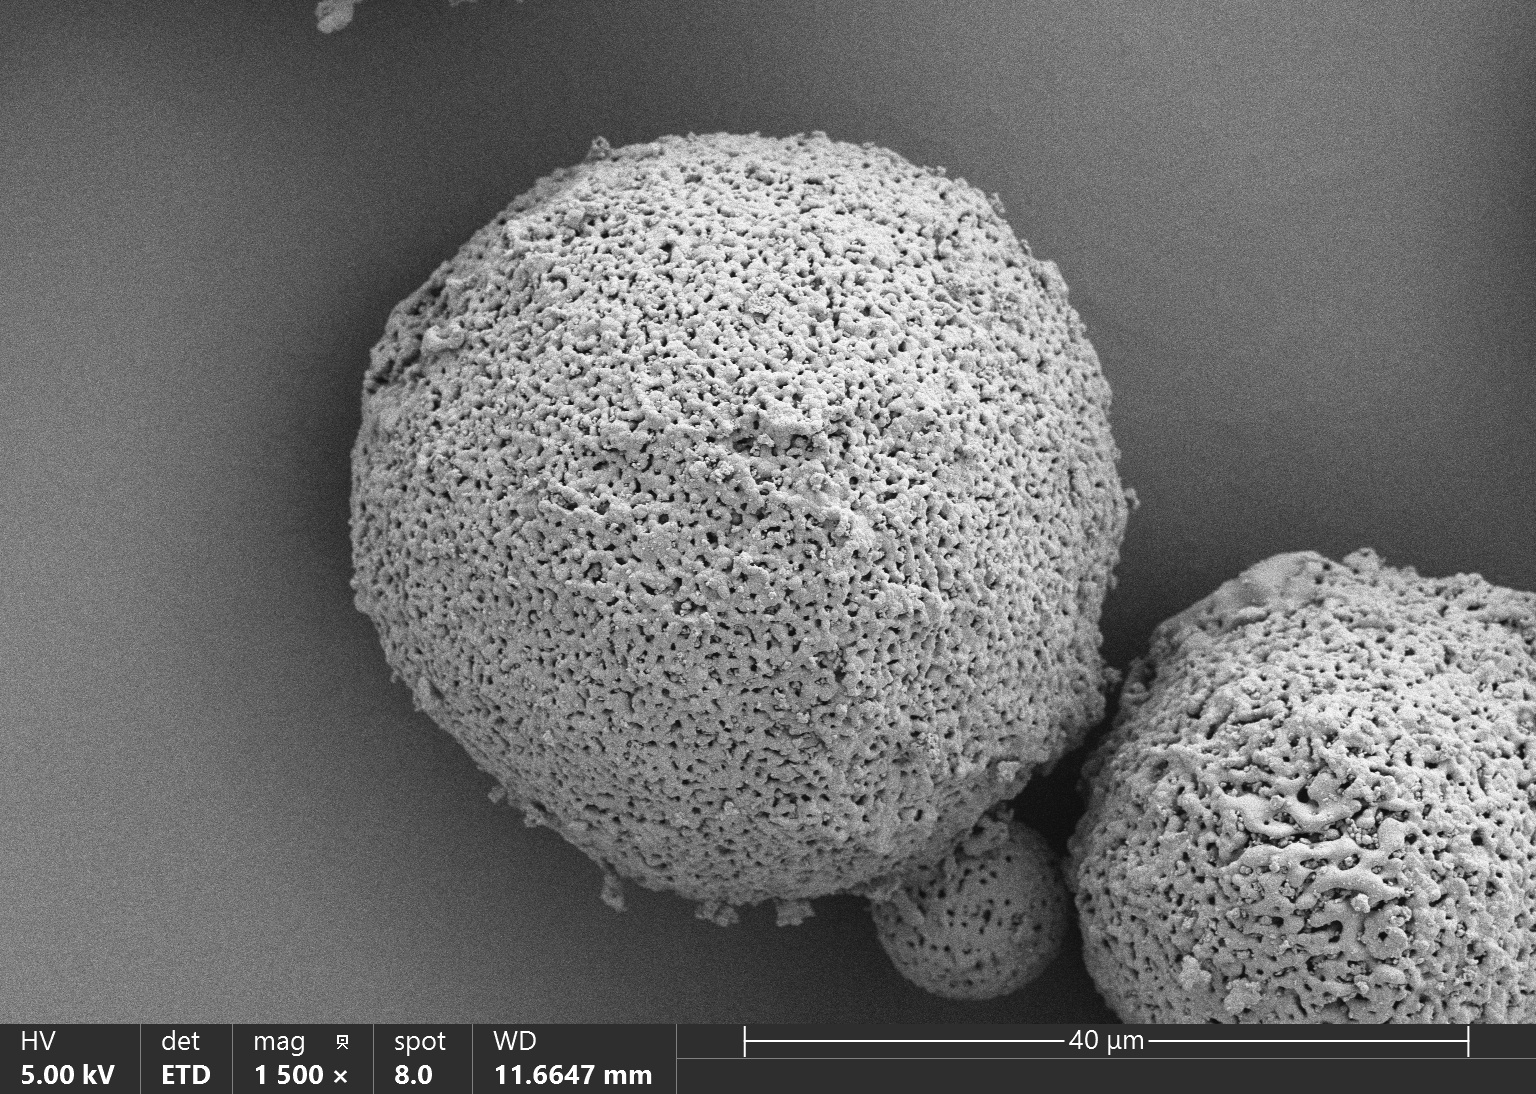

Vita Spire has developed HAp microsphere products for next-generation aesthetic fillers. We offer three different products, each varying in porosity, which corresponds to different degradation rates after injection. Our HAp microspheres provide versatile options for creating specialized, high-quality aesthetic treatments.

| HAPAI-01 | Hydroxyapatite (HAp) Microspheres for Aesthetic Injection, Type I | N/A | Details |

| HAPAI-02 | Hydroxyapatite (HAp) Microspheres for Aesthetic Injection, Type II | N/A | Details |

| HAPAI-03 | Hydroxyapatite (HAp) Microspheres for Aesthetic Injection, Type III | N/A | Details |